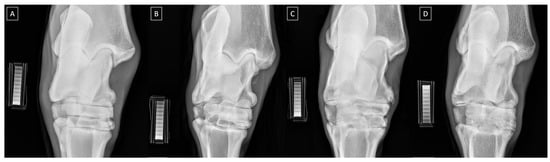

| Grade | Severity | Radiographic Signs |

|---|---|---|

| 0 | Normal | Normal width and shape of the joint space; smooth cortical bone surface; normal subchondral bone pattern; no periosteal proliferation; no intra-articular mineralization |

| 1 | Mild | Narrow and irregular joint space with osteophytes; irregular cortical bone surface with well-defined protuberance; smooth subchondral bone pattern; flat periosteal proliferation; mild intra-articular mineralization |

| 2 | Moderate | Narrow and irregular joint space with multiple osteophytes, enthesiophytes, and marked asymmetry; irregular cortical bone surface with well-defined bone proliferation; subchondral bone cyst; flat periosteal proliferation; moderate intra-articular mineralization |

| 3 | Severe | Completely narrow joint space with large osteophytes and enthesiophytes; severe deformation of cortical bone surface; subchondral bone sclerosis; flat or intense periosteal proliferation; severe intra-articular mineralization |